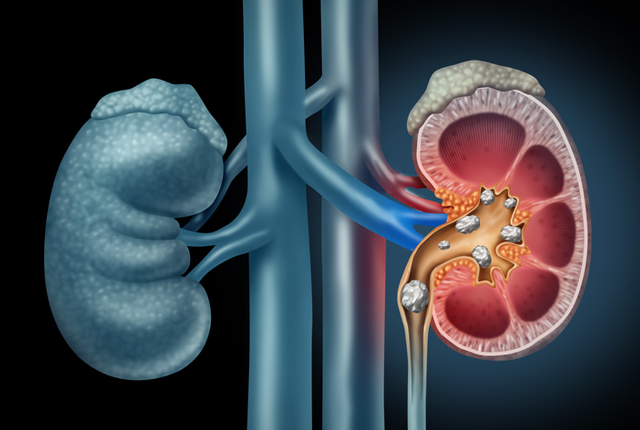

2. kép:

Vese

Egy sematikus ábrát láthatunk a veséről. A vese parenchyma 2 részből áll, a velő (medulla) és a kéreg (cortex) állományból. A vizelet a vesemedencében gyűlik össze (pelvis), ahonnan a húgyvezetéken (ureter) keresztül távozik a hólyag irányába. Láthatjuk, hogy a vesemedencében relatív nagyobb tér áll rendelkezésre mint a hugycsőben, ami miatt a fent keletkezett nagyobb kövek nagyobb eséllyel akadhatnak el a szűkebb húgycsőben. A vesének azt a részét ahol a vizeletelvezető rendszer kilép a veséből kapunak nevezik. A vesét ellátó erek is itt lépnek be illetve ki a veséből.

4. kép:

Vesekő sematikus ábra

A képen a vesekövek láthatóak mind a vesemedencében és annak kehelyvégeiben valamint a húgyvezeték kezdeti szakaszán. Az ábra jól szemlélteti, hogy az ilyen kövek hogyan zárhatják el a vizelet útját és okoznak ezzel vizeletelfolyási akadályt.